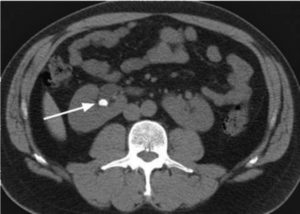

Если по каким-либо причинам камни в почках на УЗИ не удалось рассмотреть детально, особенно если они локализованы в мочеточнике, назначают КТ или МРТ почек.

Во время диагностирования на мониторе видно изображение органа в формате 3D, благодаря чему врач видит любые патологические изменения.

Зачастую МРТ или КТ почек назначают перед операцией, когда важно определить размер конкремента, его место расположения и состав. Мелкие камни на МРТ не визуализируются.